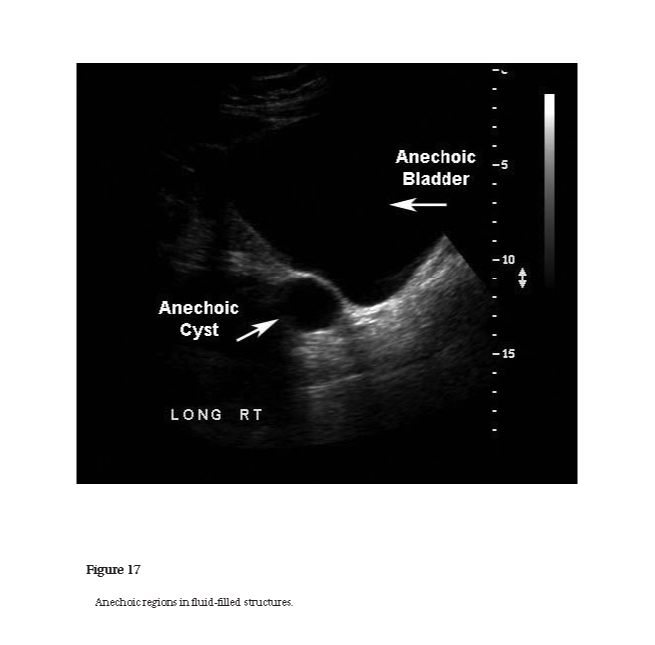

anechoic

The property of appearing echo free or without echoes in an ultrasound image. A clear cyst appears anechoic in the absence of any artifact (see Figure 17).

Figure 17